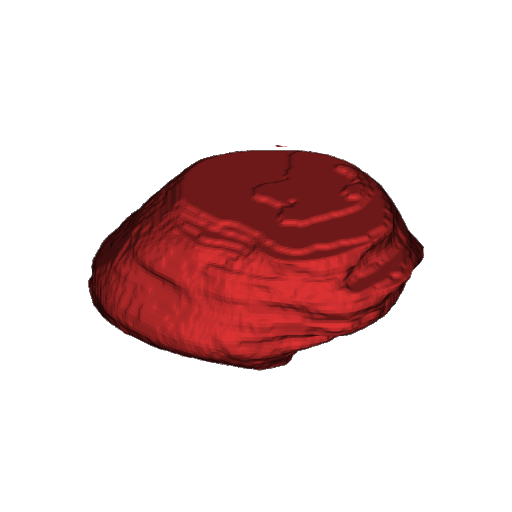

2. UDBRNet.gif

UDBRNet: A novel uncertainty driven boundary refined network for organ at risk segmentation

Riad Hassan, M. Rubaiyat Hossain Mondal, and Sheikh Iqbal Ahamed

PLOS ONE, Jun 2024